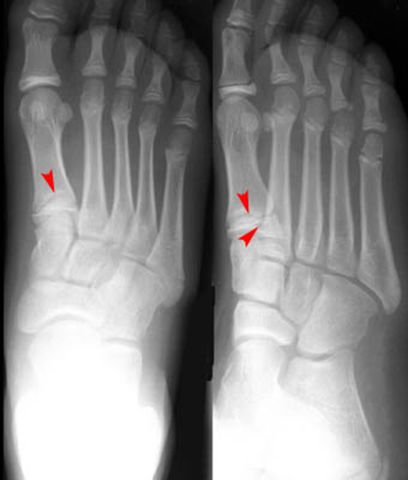

跖骨骨折